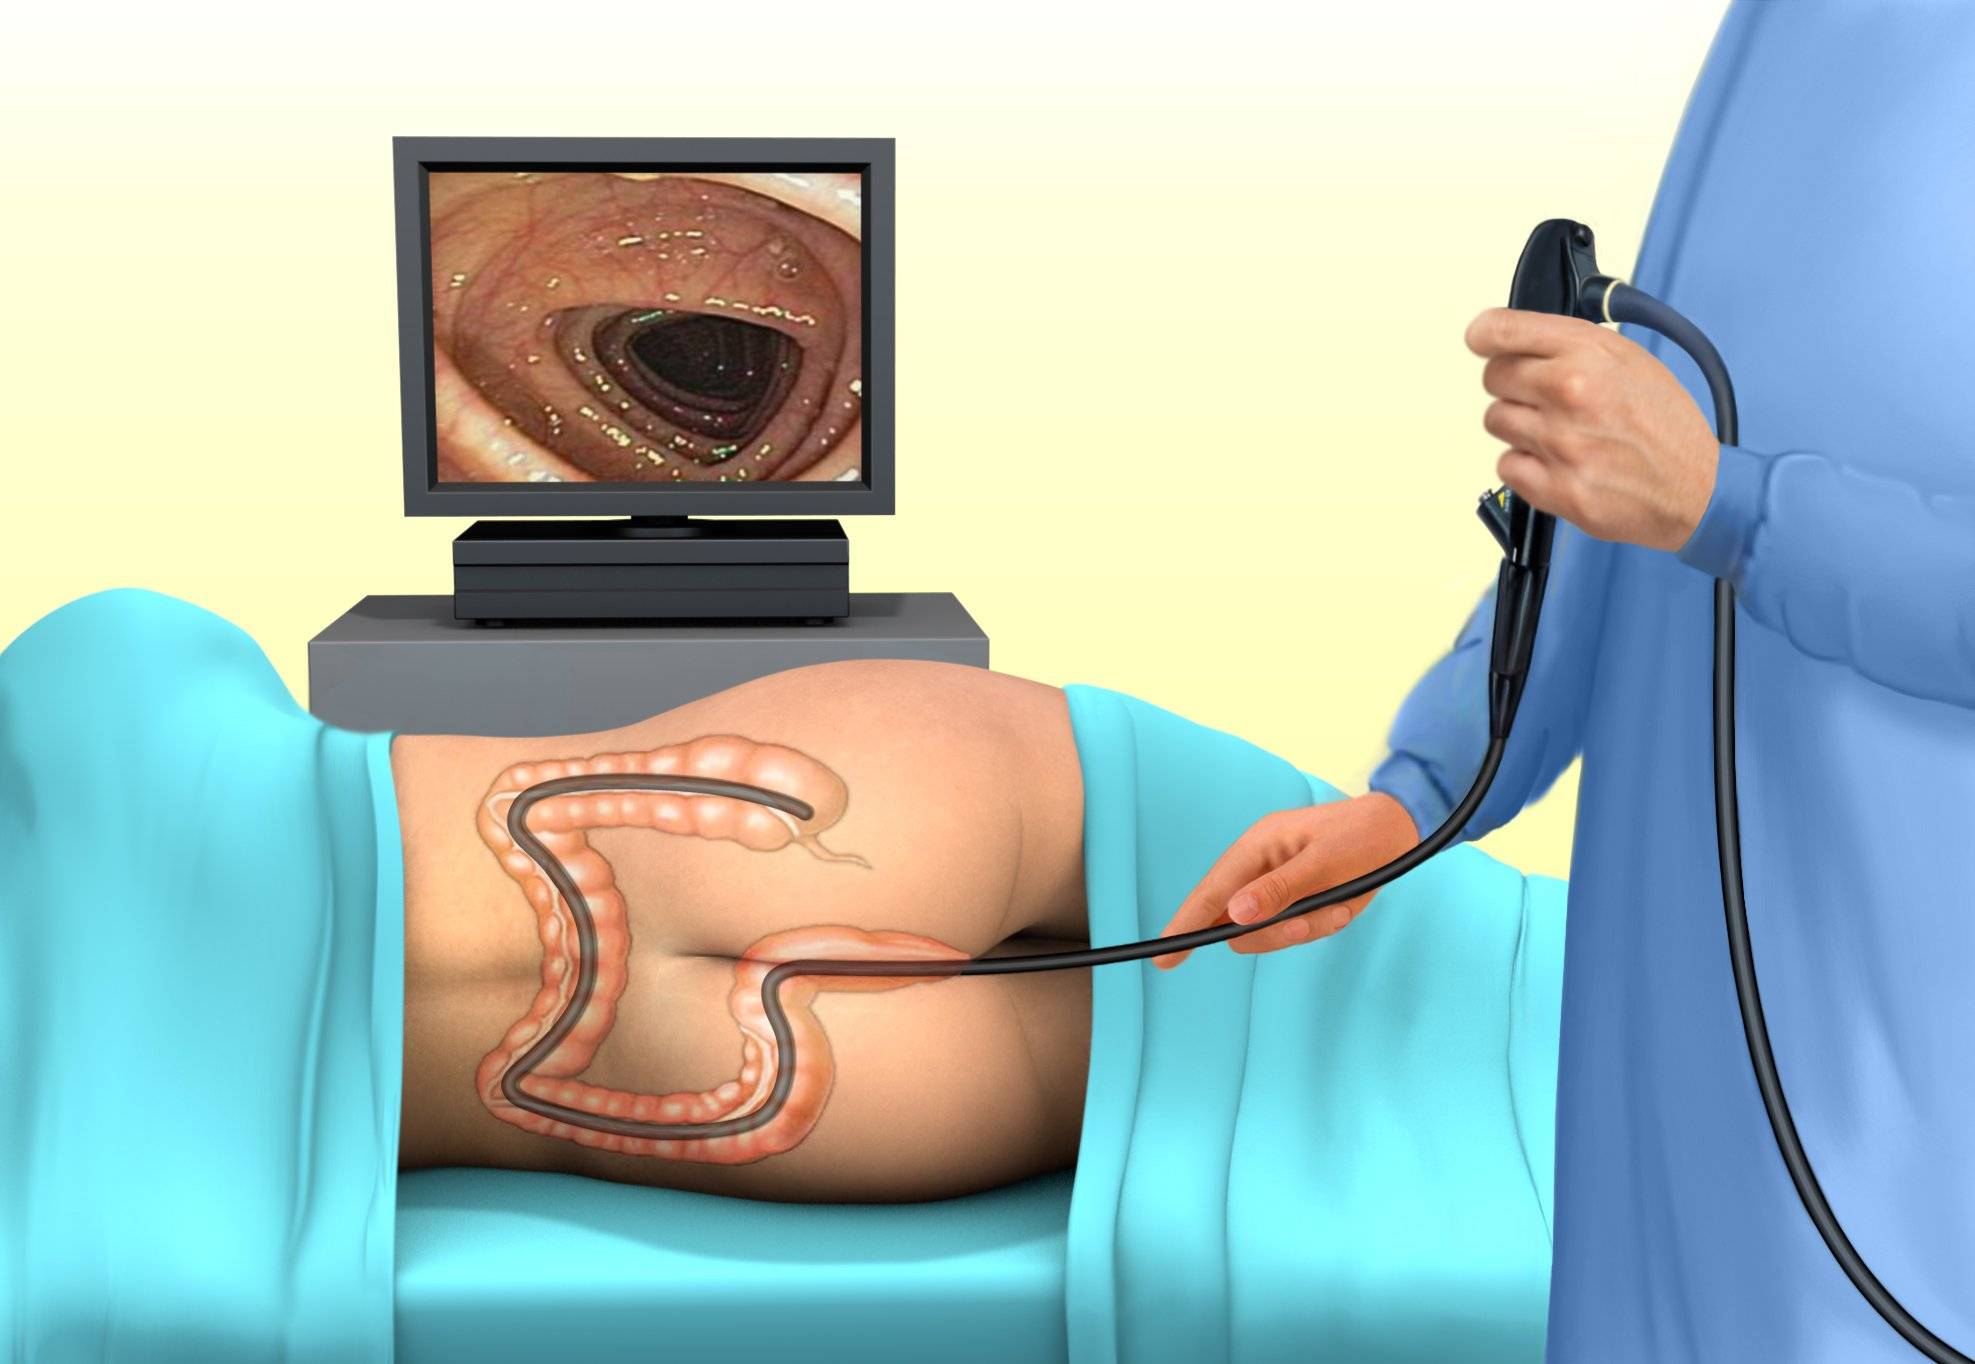

Подготовка к ирригоскопии: необходимые препараты